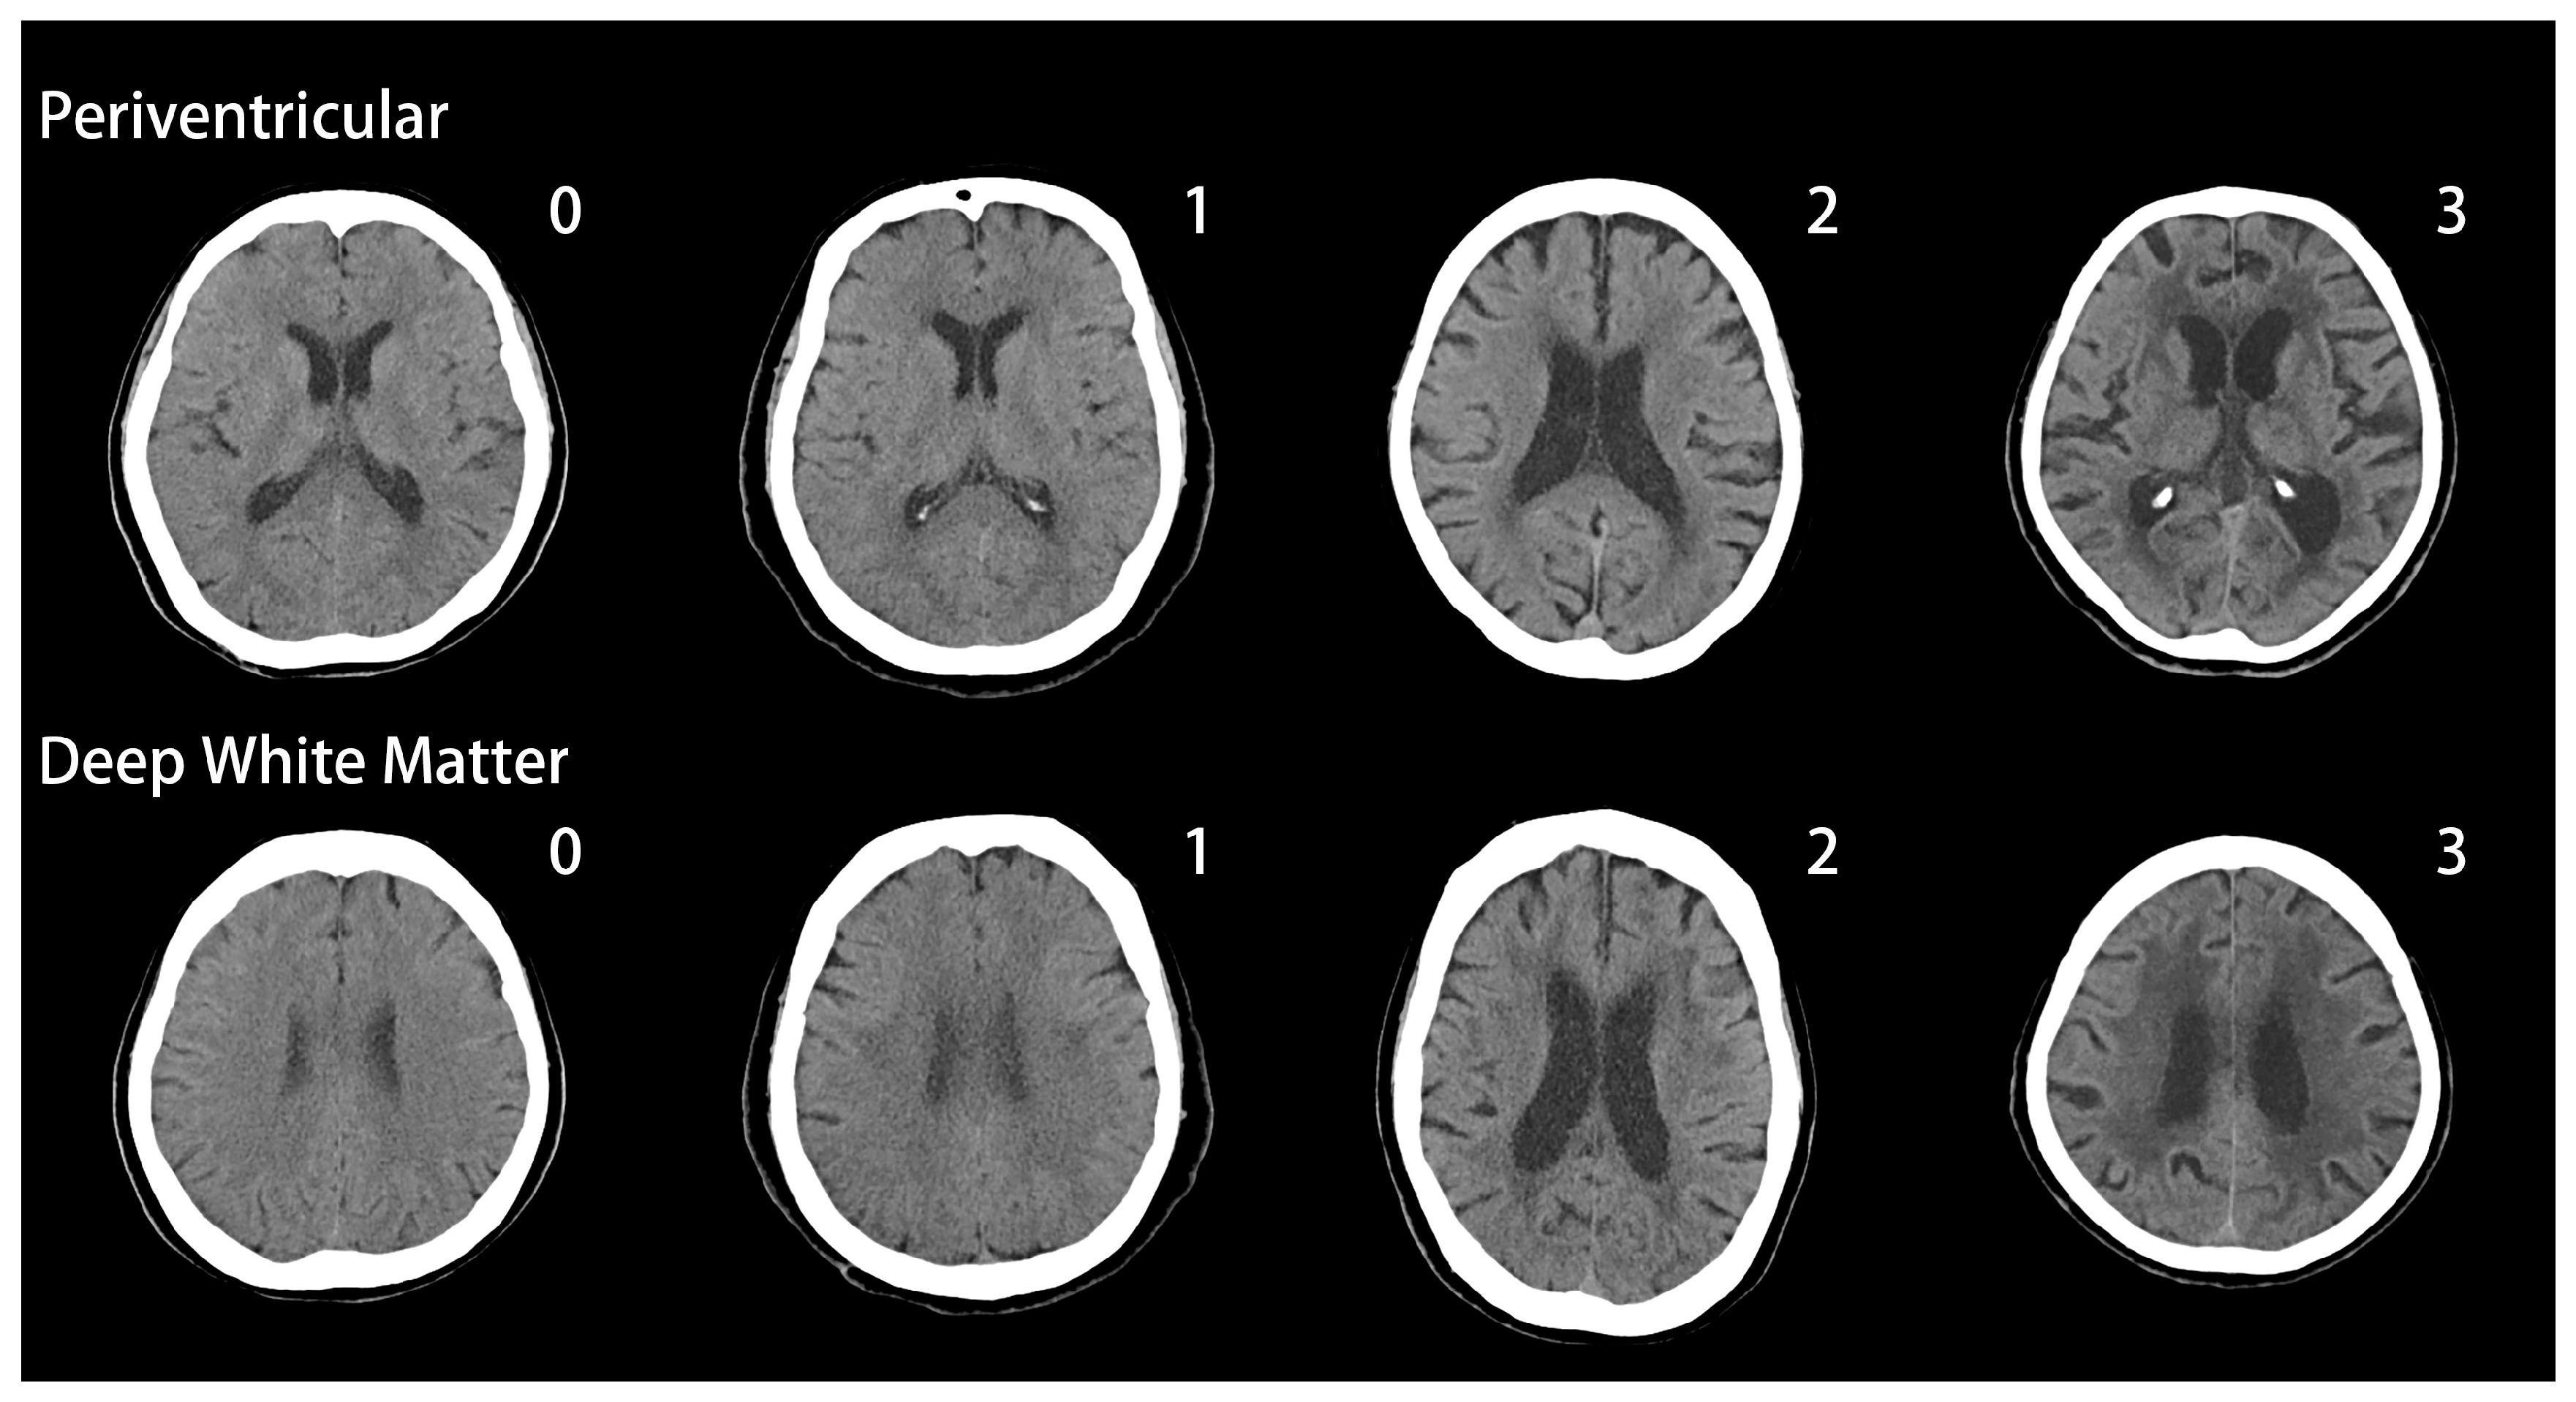

Fazekas grades. Лейкоареоз головного мозга мрт. Перивентрикулярный лейкоареоз мрт. Лейкоареоз Фазекас. Лейкоареоз на кт.

Fazekas grades. Лейкоареоз головного мозга мрт. Перивентрикулярный лейкоареоз мрт. Лейкоареоз Фазекас. Лейкоареоз на кт.

Fazekas grades. Лейкоареоз головного мозга мрт. Перивентрикулярный лейкоареоз мрт. Перивентрикулярный лейкоареоз головного мозга на кт. Лейкоареоз Fazekas 1 что это.

Fazekas grades. Лейкоареоз головного мозга мрт. Перивентрикулярный лейкоареоз мрт. Перивентрикулярный лейкоареоз головного мозга на кт. Лейкоареоз Fazekas 1 что это.

Fazekas grades. Лейкоареоз на кт. Лейкоареоз головного мозга мрт. Перивентрикулярный лейкоареоз. Перивентрикулярный лейкоареоз мрт.

Fazekas grades. Лейкоареоз на кт. Лейкоареоз головного мозга мрт. Перивентрикулярный лейкоареоз. Перивентрикулярный лейкоареоз мрт.

Fazekas grades. Перивентрикулярный лейкоареоз. Лейкоареоз Fazekas 1 что это. Лейкоареоз на кт.

Fazekas grades. Перивентрикулярный лейкоареоз. Лейкоареоз Fazekas 1 что это. Лейкоареоз на кт.

Fazekas grades. Лейкоареоз головного мозга на кт. Лейкоареоз на кт. Перивентрикулярный лейкоареоз на кт. Лейкоареоз головного мозга мрт.

Fazekas grades. Лейкоареоз головного мозга на кт. Лейкоареоз на кт. Перивентрикулярный лейкоареоз на кт. Лейкоареоз головного мозга мрт.

Fazekas grades. Перивентрикулярный лейкоареоз на кт. Fazekas 1. Фазекас мрт. Лейкоареоз Fazekas 1 что это.

Fazekas grades. Перивентрикулярный лейкоареоз на кт. Fazekas 1. Фазекас мрт. Лейкоареоз Fazekas 1 что это.